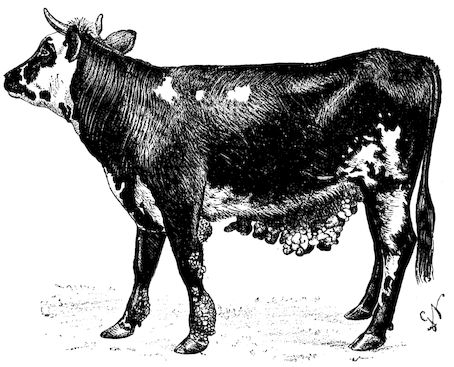

Fig. 2.—Horse suffering from osseous cachexia.

2. The second phase is characterised by more precise signs, which become almost pathognomonic. Difficulty in rising is added to the already existing tendency to remain lying, and to the interference with movement.

When lying down the patient no longer responds to the trifling stimulus, which a healthy animal needs to cause it to rise. It remains languid and apparently lazy, though in reality it experiences pain and difficulty on attempting to get up. The least muscular effort when lying down often causes it to moan, as do efforts to change its position or to walk. Even when standing still, it may appear to be in pain, and patients often assume a position similar to that of a horse suffering from laminitis.

At the end of this second phase, swellings appear, due to synovitis or arthritis of the extremities, synovitis of the sesamoid or navicular sheaths or to inter-phalangeal arthritis or arthritis of the fetlock joint. Weakness becomes marked, and the appetite is very irregular.

10Secretion of milk diminishes or ceases and abortion is not uncommon.

3. The third phase is characterised by fractures, and it is this peculiarity of the disease which has procured for it the names of fragilitas ossium, and osteoclastia. These fractures may affect any portion of the skeleton. Animals so suffering sometimes break a leg whilst trotting or the pelvis in simply jumping over a ditch; a collision with a fixed object like the jamb of the stable door, or a fall on the ground, may result in the fracture of one or several ribs.

Fig. 3.—Pig suffering from osseous cachexia (fourth stage).

Such shocks would be of no importance to a healthy animal, but to one suffering from osseous cachexia, any violence, or even the slightest muscular effort may be followed by fracture of the gravest character, involving even the vertebral column. In cows the pelvis, femur, and tibia are most frequently injured.

In horses, particularly in riding horses, fractures are commonest in the region of the forearm, cannon bone, and anterior phalanges. So extremely fragile are the bones at this stage that the horse represented herewith broke twelve ribs at one time by simply falling on its side. It is interesting to note that such fractures are never accompanied by any extensive bleeding. They have little tendency to repair, no real callus formation occurs, and on post-mortem examination one often finds the ends unconnected by temporary callus, worn, and rounded by reciprocal friction.

At this stage but under other circumstances, the animals show great reluctance to rise, remaining down for twelve to twenty-four hours without shifting their position. If forced to get up, they stand as though fixed in one position, the respiration and circulation become rapid, and they soon grow tired and fall.

114. The fourth phase, or period of osteomalacia, i.e. softening of the bones, is also the last. It is rarely seen in large animals like horses and oxen, because accidents so often accompany the preceding stages and necessitate slaughter; but it is common in goats and pigs.

In this phase the bones become elastic, soft and depressible, yielding to the pressure of the operator’s fingers.

Fig. 4.—Deformity of the face in the horse shown in Fig. 2.

The flat bones are particularly liable to this change, which is common to domesticated animals. The bones of the head are the first to suffer; later those of the pelvis. The lower jaw becomes swollen, particularly about the centre of the branches which may attain three, four, or five times, their normal thickness.

The depression in the submaxillary space disappears. The upper jaw undergoes similar changes, becoming deformed and thickened until the cavities of the sinuses and the hollow appearance of the palate are lost, while the face is so changed that it cannot be recognised as that of a horse, goat, etc.

The molar teeth are almost buried, their tables alone being visible at the bottom of a depression, the edges of which rise above the neighbouring parts (pig).

Mastication is clearly impossible, the jaws appear paralysed, the muscles powerless, and only swallowing is possible, a fact which explains why life is only prolonged to this stage in animals which can be fed with a spoon or bottle (pigs and goats). The bones of the cranium, although greatly changed in texture, are always less deformed than those of the face.

The changes are such that it is often easy with a mere post-mortem knife to cut the head completely in two. Osseous tissue, properly so-called, has disappeared.

All the constituent tissues, with the exception of the skin and muscles, i.e., the bone, periosteum and aponeuroses, have the appearance and consistence on section of the fibro-lardaceous tissue seen in chronic inflammation.

The following is a condensed description of the disease as given by Law:—

Symptoms. Poor condition or even emaciation, with very visible projection of the bones. The coat is rough, skin tense, inelastic and 12hidebound, appetite variable, sometimes impaired, and nearly always perverted (or depraved) so that the patient will lick the manger continually or pick up and chew all sorts of objects: bones, leather, clothing, wood or iron, stones, etc. The amount of food consumed may, however, be up to the normal. The most marked feature is the difficulty and stiffness of locomotion.... Temperature and yield of milk may remain normal.

“Later, appetite and milk secretion fail, temperature rises a degree or two, the animal refuses to rise, remaining down twelve to twenty-four hours at a time, and ... when rising ... remaining on the knees for a time, moaning and indisposed to exert itself further. At this stage many cases begin to improve and may get well in five or six weeks. Some will remain down for several weeks and finally get up and recover. With constant decubitus, however, the animal falls off greatly, becoming emaciated and weak, the appetite may fail altogether, and the patient is worn out by the persistent fever, nervous exhaustion and poisoning from the numerous bed-sores ... which are common over the bony prominences. It is in these last conditions, above all, that fractures and distortions of the pelvic bones, and less frequently of the bones of the legs occur.”

Fig. 5.—Head of a pig suffering from osseous cachexia.

“The disease may advance for two or three months, and in case of pelvic fractures and distortions, there may be permanent lameness, and dangerous obstruction to parturition, even though the bones should acquire their normal hardness through the deposition of lime salts.”

Fig. 6.—Osseous cachexia. This condition developed in two months, the last month of gestation and the first of lactation.